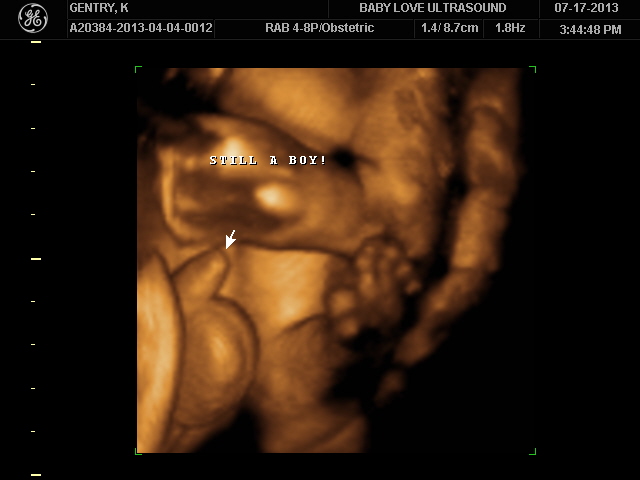

16 Week Gender Scan